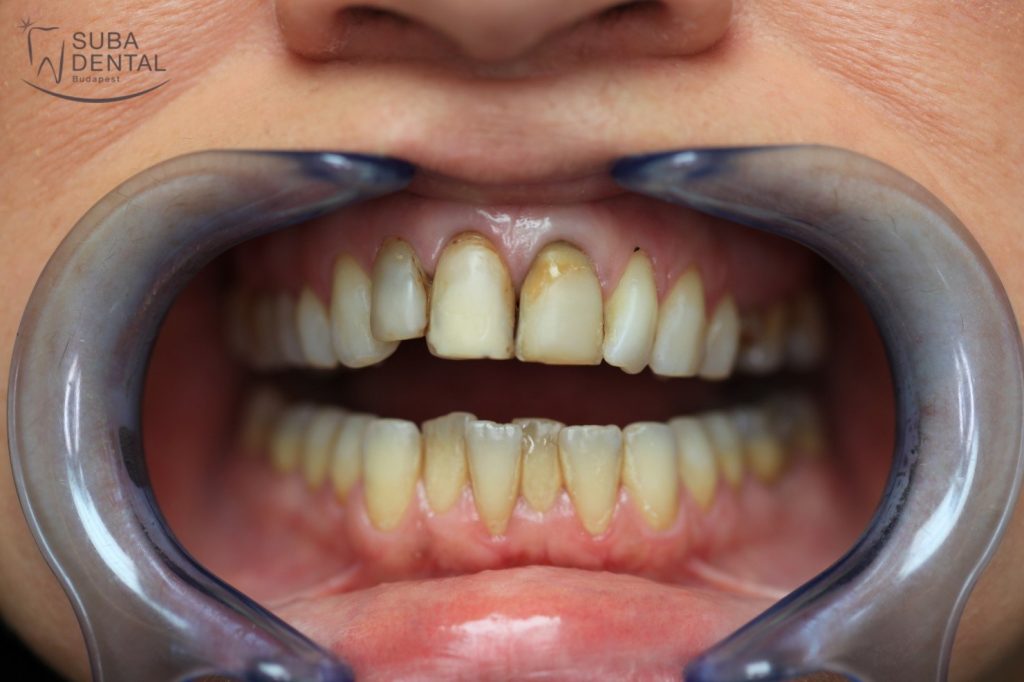

Our female patient, aged 37, reported to our clinic with the following problems:

- She had become rather reclusive on account of her teeth.

- Restoration of aesthetics was a top priority so she could feel at ease to smile again.

- She sought to have teeth of uniform colour and shape.

Before